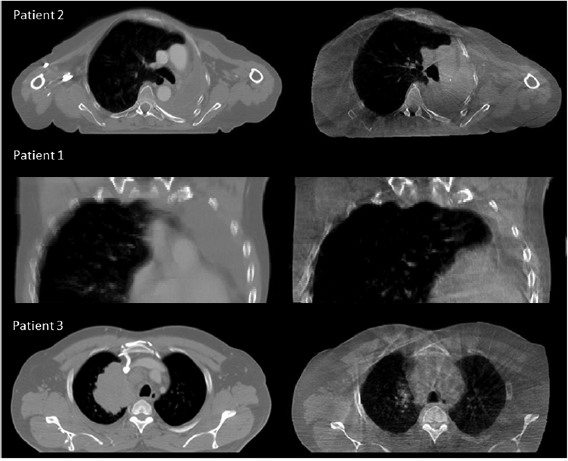

Table 1. Patient summary. Examples of anatomical charge are provided at figure 1.

Figure 1. Examples of minor (Patient 2), moderate (Patient 1) and major (Patient 3) anatomical changes. For each patient the pCT is shown on the left and the CBCT is shown on the right.

Download figure:

Standard image High-resolution imageThe CT images were acquired on a GE Lightspeed Widebore 16 slice CT system (GE Healthcare, Buckinghamshire, UK). For one of the seven patients, the pCT and rCT were helical images and for the remaining six they were 4DCT Average Intensity Projection (AvIP) images. In all cases the pCT and rCT were the images on which dose calculations were originally performed. CBCT images were acquired using the Varian OBI version 1.4 (Varian Medical Systems, Palo Alto) in full rotation half-fan mode with the following parameters; 45 cm FOV, 110 kV, 20 mA and 20 ms. The CBCT acquired immediately prior to the replan was selected for analysis; the time delay between acquisition of the CBCT and rCT varied between zero and five days.